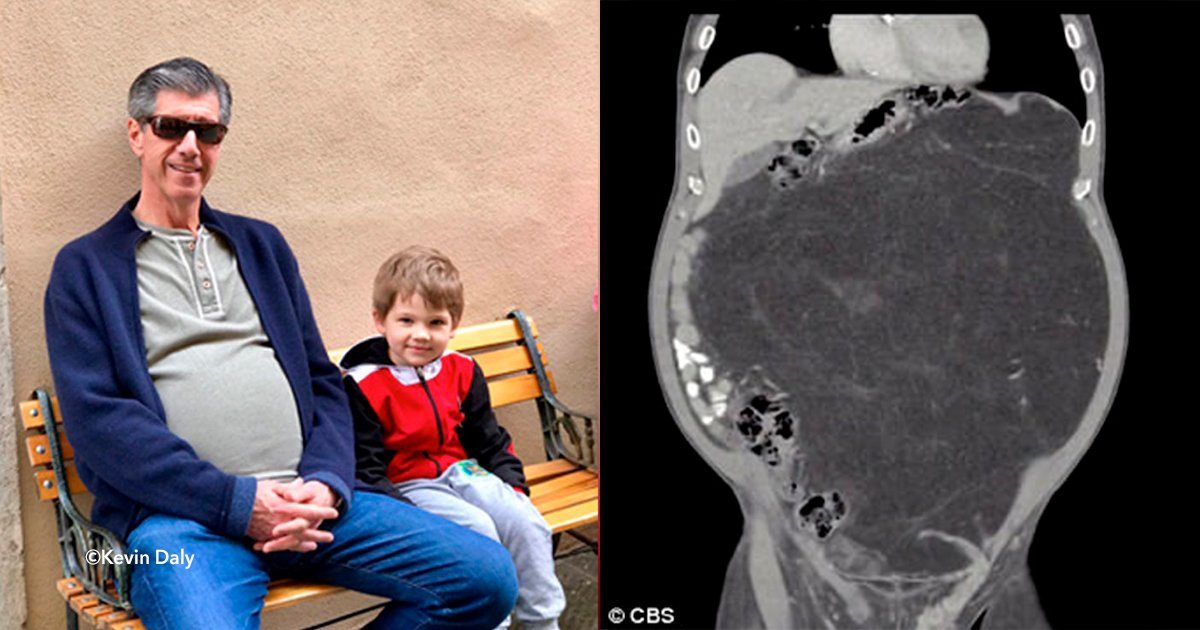

Kevin Daly, de 63 años, pensaba que estaba muy gordo, por lo tanto comenzó a realizar ejercicios y a comer de forma saludable.

El hombre logró bajar de peso, pero su panza seguía exactamente igual.

Eso alarmó muchísimo a este hombre de Hoboken, Nueva Jersey.

“Pero después de la pérdida de peso, no perder un gramo de mi estómago, no tenía lógica”, dijo Daly, y los doctores estuvieron de acuerdo, por lo tanto decidieron realisarle algunas pruebas.